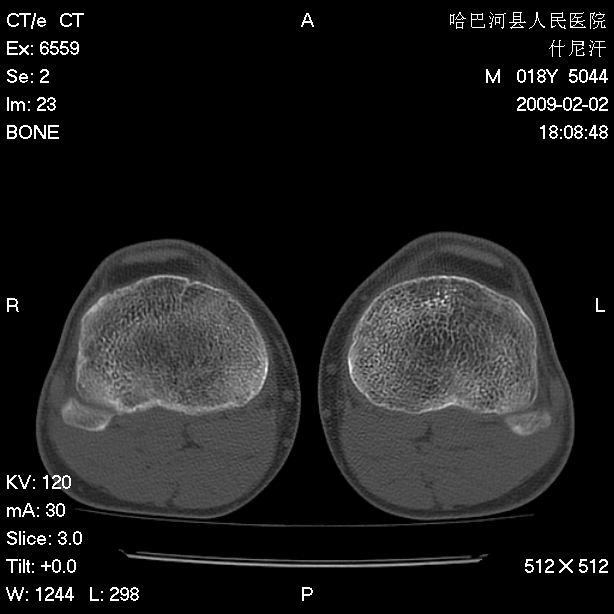

标题: CT17889:外伤后右膝关节反复疼痛3年余 [打印本页]

标题: CT17889:外伤后右膝关节反复疼痛3年余

ct未见明显异常。关节腔未见明显积液,半月板未见明显撕裂。但最好还是mri看看韧带及半月板情况。